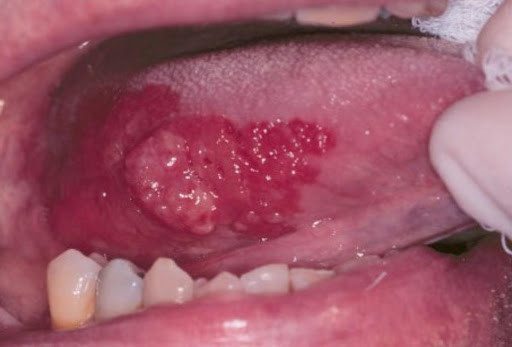

Erythroplakia. This is a red patch that can be both flat or slightly raised. When scraped, it bleeds easily.

Erythroleukoplakia. A combination of leukoplakia and erythroplakia, it has both red and white areas.

Oral lesions like erythroplakia may initially be painless, but their red appearance warrants further evaluation. So regular examinations of your mouth are critical for early detection.

A dental professional can perform a thorough soft tissue and head and neck exam to detect possible lesions. Research from Jefferson University Hospitals has found that erythroplakia is generally seen on the tongue or the mouth floor. You can also find lesions in the back of the throat and just behind the last molars.